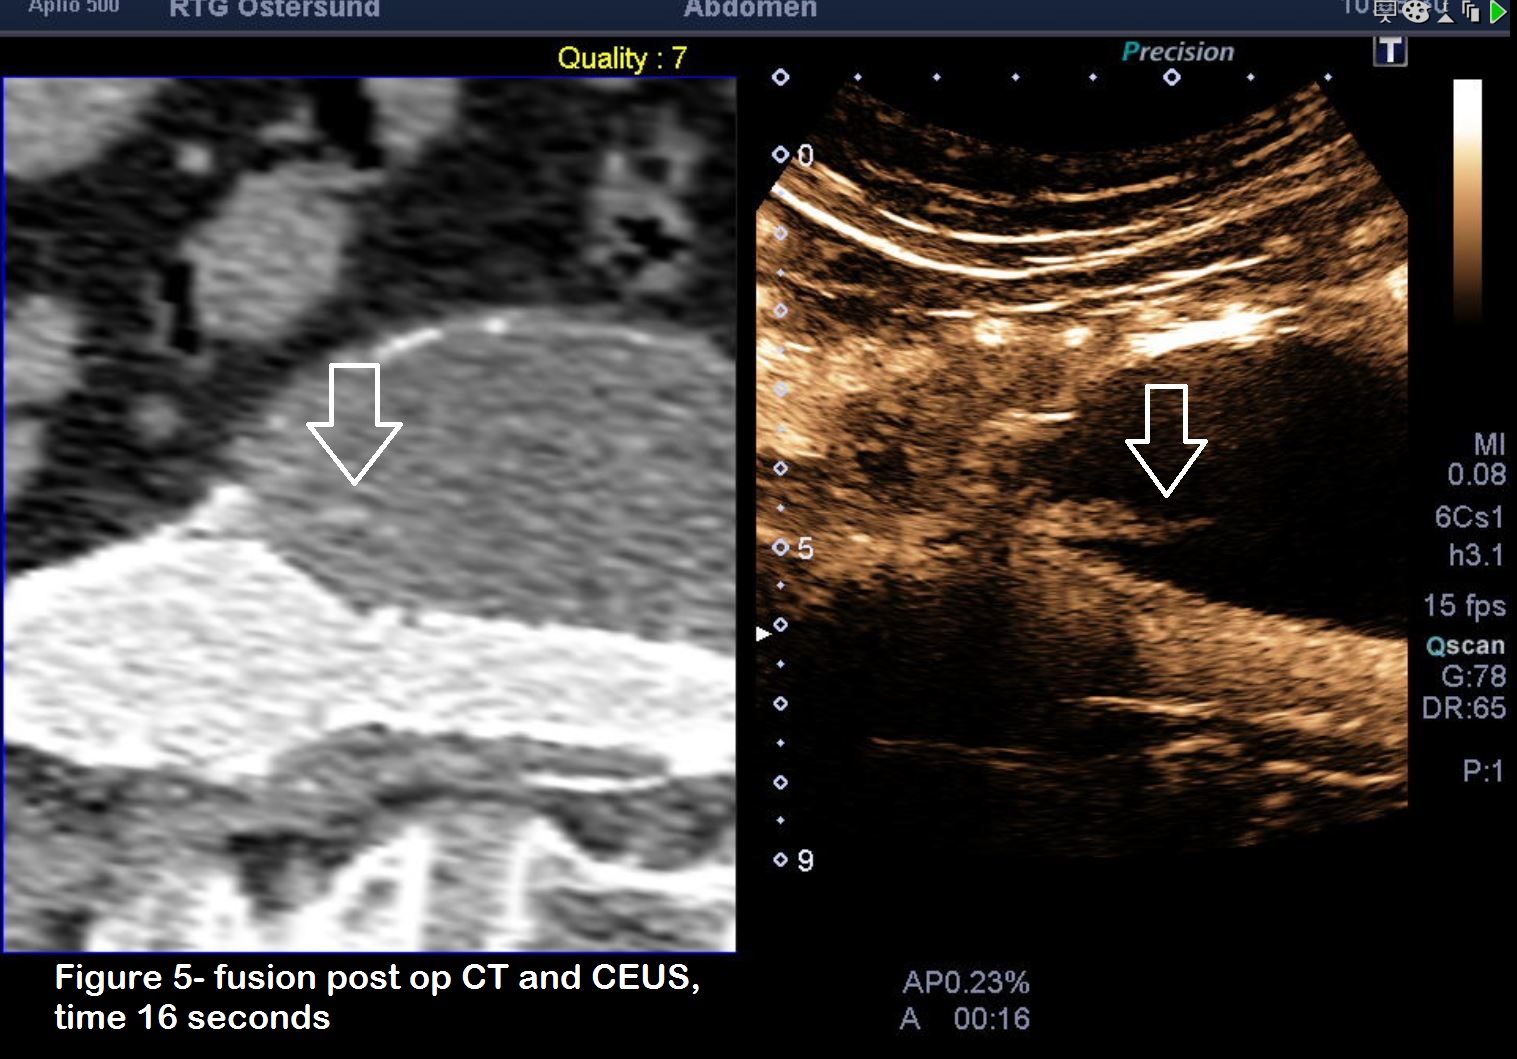

Figure 5: CEUS with fusion ultrasound. A total of three separate injections of Sonovue 1.5 ml intravenously were undertaken. The first injection, longitudinal scan of the aorta, shows a small endoleak type 1A at the top of the stent. Typical for this type of leak is that it occurs simultaneously as the first flow of contrast appears within the aorta/stent.